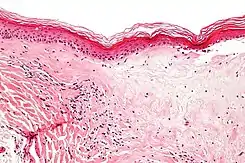

Se puede hacer una biopsia de la piel afectada para confirmar el diagnóstico. Cuando se hace una biopsia, la hiperqueratosis, la epidermis atrófica, la esclerosis de la dermis y la actividad de los linfocitos en la dermis son hallazgos histológicos asociados con LS.[21] Las biopsias también se revisan para detectar signos de displasia.[22]